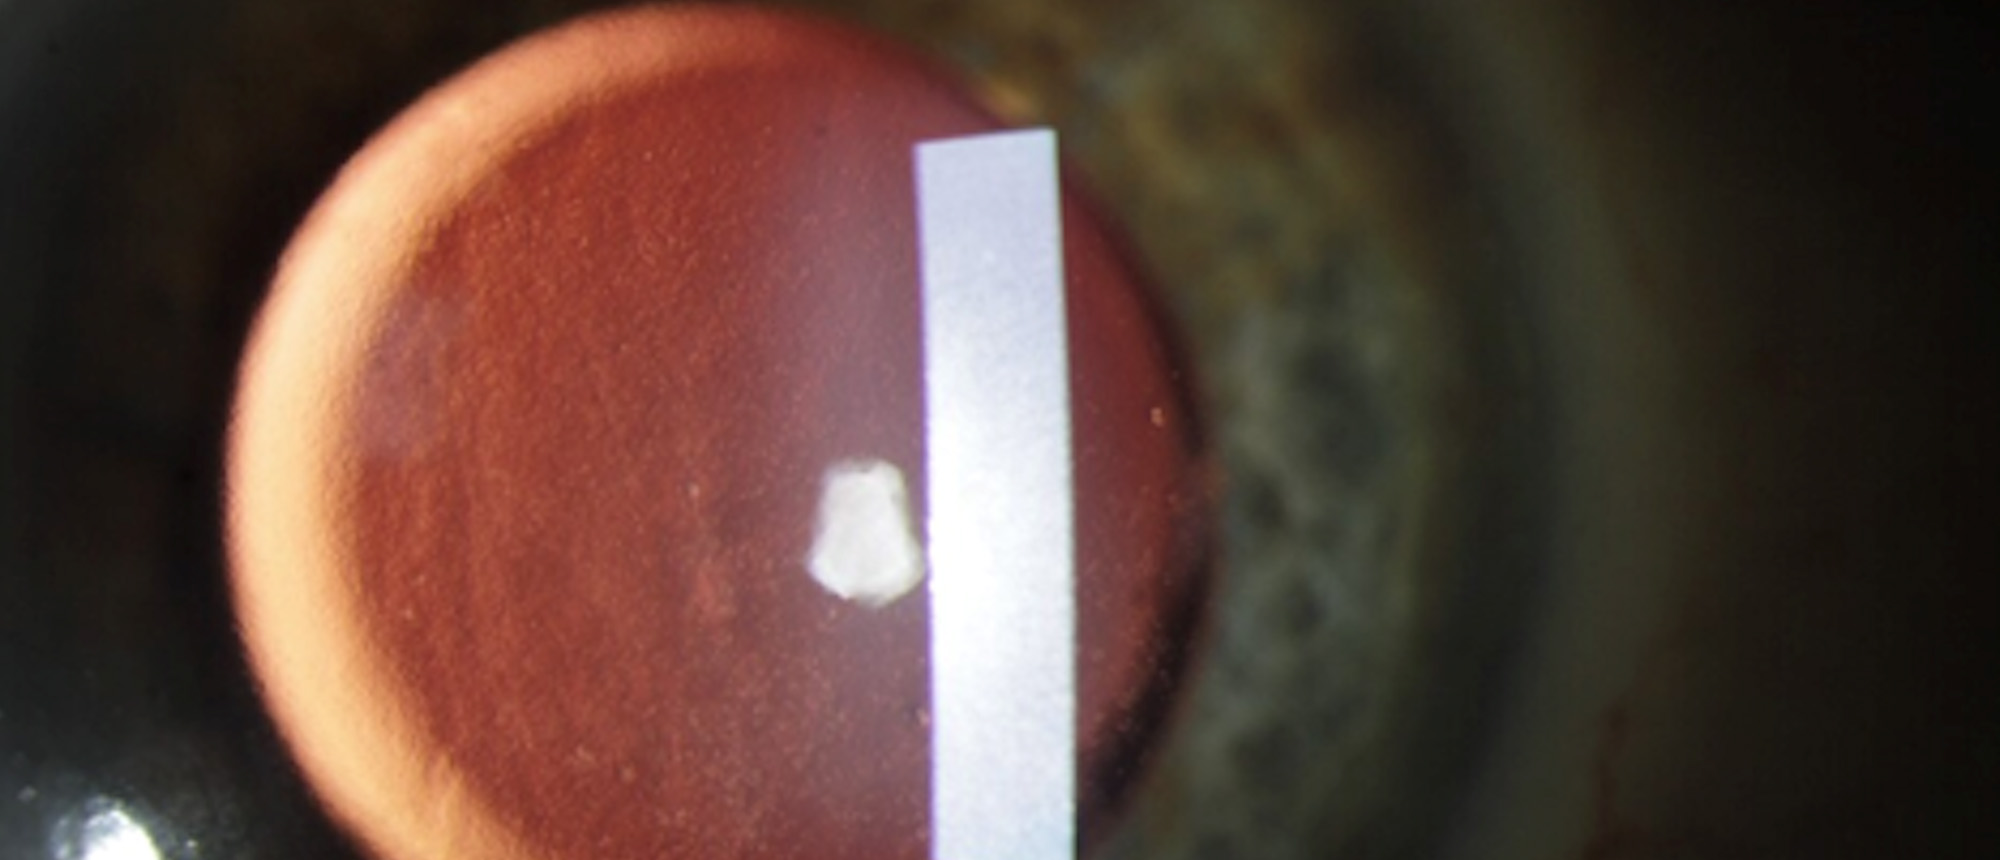

Morgagnian Cataract, Pseudoexfoliation Syndrome, Phacolytic Glaucoma

Specialty: Cataracts and Intraocular Lenses

Type: Ophthalmic Images

Include in Catalogue?: Yes

Original Contributor(s): Jesse D. Sengillo, MD; Jonathan D. Tijerina, MD, MA; Luiz E. Vazquez, MD, PhD

Presenter/Faculty: Sengillo, Tijerina, Vazquez

Slit lamp photos and UBM demonstrating a Morgagnian Cataract in a patient with Pseudoexfoliation Syndrome and Phacolytic Glaucoma.